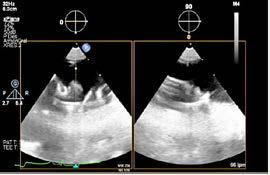

Mujer de 73 años con antecedentes de hipertensión arterial, trombopenia en contexto de lupus eritematoso sistémico, episodio de hipotiroidismo inducido por amiodarona y fibrilación auricular (FA) en estrategia de control de frecuencia cardiaca, anticoagulada con antivitamina K. Como fundamental antecedente cardiológicos destaca una valvulopatía reumática con afectación mitral, que inicialmente se reparó en 1997 mediante abordaje transapical (dejando como secuela aneurisma apical) y se recambió en 2007 por prótesis mecánica. Posteriormente, fue diagnosticada de doble lesión aórtica reumática con estenosis severa e insuficiencia ligera, con fracción de eyección preservada, pero insuficiencia tricuspídea severa e hipertensión pulmonar de predominio poscapilar. Ingresó programada para implante percutáneo de válvula aórtica (TAVI) vía transfemoral, con los principales condicionantes de bloqueo de rama derecha y altura límite de tronco coronario izquierdo (TCI), por lo que se administró clopidogrel 600 mg previamente al procedimiento.

Previo implante de marcapasos temporal yugular derecho se llevó a cabo el procedimiento. Durante la liberación de prótesis mediante inflado del balón, tuvo lugar la embolización supra-anular de la misma, dejando por un lado una insuficiencia aórtica severa y por otro lado ocluyendo parcialmente ambos troncos coronarios. Empleando doble acceso radial se enganchó la prótesis mediante un lazo y se desplazó hacia aorta ascendente, dejando hueco para la colocación de una segunda prótesis en situación correcta y evitando la oclusión de los ostium coronarios y troncos supra-aórticos. En ausencia de bloqueo auriculoventricular se retiró el marcapasos temporal, se evidenció un hematoma yugular derecho y, a través de analítica, se detectó anemización de 2,5 puntos. Mediante angiografía, se descartó enfermedad coronaria y, mediante ecocardiograma transesofágico, se confirmó normoposición de la prótesis, objetivándose al mismo tiempo una disección aórtica.

DIAGNÓSTICO Y ACTITUD INICIAL

Se realizó una tomografía computarizada (TC) con contraste de forma emergente, que mostró una disección aórtica iatrogénica tipo A focal de origen en la zona 0 del cayado con extensión al tronco braquiocefálico derecho (1) sin afectar al resto de troncos supra-aórticos, cayado o aorta descendente (Figuras 1 y 2); además del hematoma

yugular con signos de sangrado activo. La paciente fue trasladada a la unidad de cuidados críticos cardiológicos. Teniendo en cuenta el alto riesgo hemorrágico (necesidad de anticoagulación permanente, administración de clopidogrel previa al TAVR y sangrado activo cervical), el alto riesgo quirúrgico y la ausencia de compromiso neurológico y hemodinámico se optó por manejo conservador (2,3) con monitorización estrecha mediante técnicas de imagen cardiaca y control estricto de la presión arterial (4).

Figuras 1 y 2: Prótesis aórtica migrada y disección aórtica focal tipo A, de origen en la curvatura menor del arco aórtico (zona 0) hasta la bifurcación de la arteria braquiocefálica derecha; sin afectación de del resto de troncos supra-aórticos, del resto del cayado aórtico o de la aorta descendente.